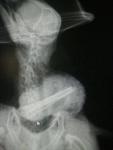

Фотоиллюстрация по теме - операция у сапсана.

10505486_739157486147834_6349199862154872844_n.jpg 10492347_739158376147745_212022230255580231_n.jpg 10418391_739153432814906_7416347863088749043_n.jpg 10524328_739158542814395_8957600941590268724_n.jpg

10421427_739158602814389_6841834848738938404_n.jpg